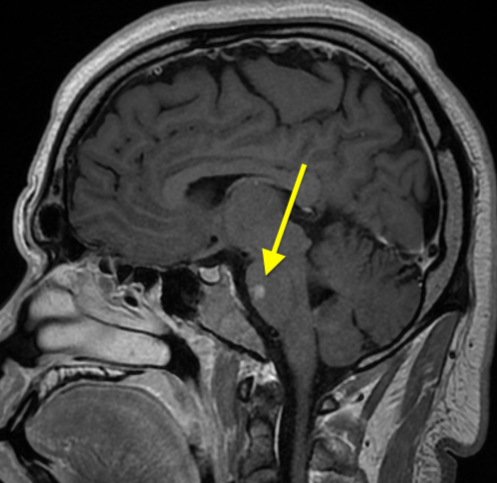

MRI of the brain repeated 4 days later showed no change in the signal abnormalities involving the left centrum semiovale and left periatrial white matter. Abnormal signal involving the pons bilaterally was demonstrated (Figures 3 and 4). Findings of MRI of the cervical and thoracic spines were normal.

Figure 3. MRI scans 4 days later showed abnormal signal involving the pons.